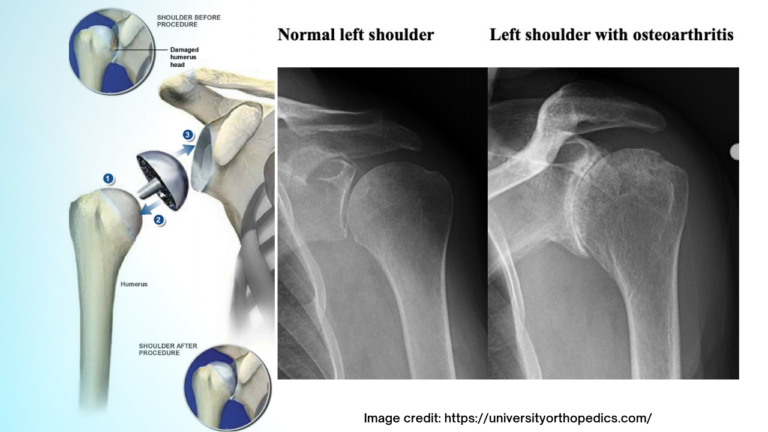

Karen was so happy with her results that she came back for her other shoulder! Today she showed us some of the new tricks! We are happy she was able to regain function after her shoulder replacement (resurfacing) procedure. What is shoulder resurfacing ? Shoulder resurfacing, also known as a humeral head resurfacing, involves replacing… [Read More]